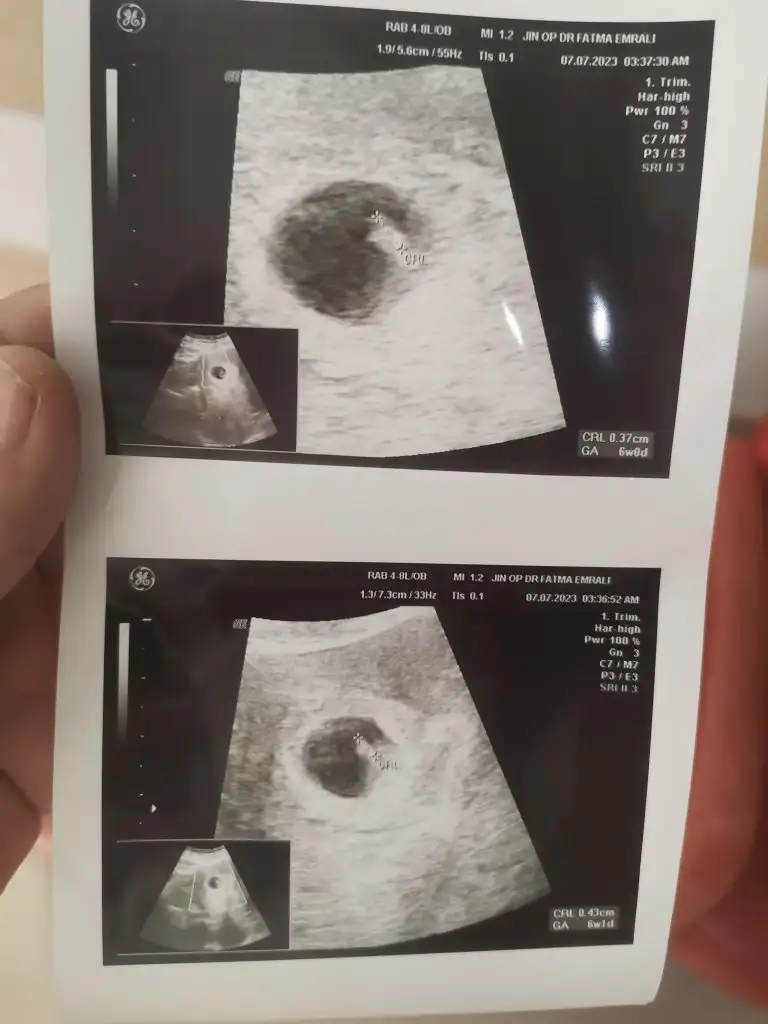

Hepsi karından çekim. Sizden yorum bekliyorum. 1 ay sonra net belli olacak inşallah. 6 haftalık ultrason, 11 haftalık ultrason ve 14 haftalık var. 16 da kendini göstermedi bacakları kapalıydı. Ayrıntılı ultrasonda belli olur artık dedi doktorum. Sizlerin de tahminini bekliyorum.